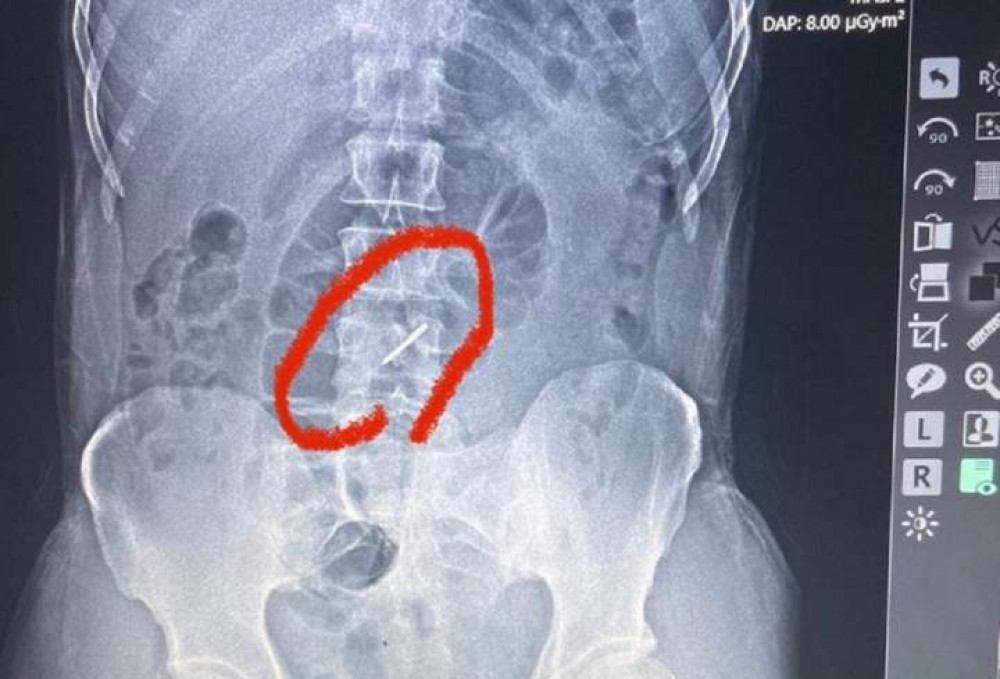

Медикам госпіталю боєць сказав, що у нього, мабуть, радикуліт, бо дуже болить поперек і вже кілька днів тримається висока температура. Як розповів ZAXID.NET лікар військово-польового госпіталю, львівський судинний хірург Тарас Кобза, бійця (його ім'я не розголошують з військових міркувань) скерували на рентген, аби чітко встановити причину болю. Лікарі були шоковані побаченим на рентгенівському знімку.

«Під час обстрілу елемент касетної бомби, так звана «стрілка», потрапила у ліве підребер’я, зламала два хребці у поперековому відділі хребта і застрягла у хребті», – каже Тарас Кобза.

Уламки зламаних хребців могли ушкодити нерви, судини, але, на щастя, цього не сталося. Боєць прийшов у польовий госпіталь своїми ногами і навіть не підозрював, що у його хребті застряг елемент касетної бомби.

«Боєць потрапив під обстріл ще 13 липня, а до нас звернувся лише на початку серпня. Він практично три тижні воював зі зламаним хребтом», – каже Тарас Кобза.

«Стрілка», що зламала бійцю хребці, влучила у підребер’я, а у тому місці у чоловіка є кілька родимок. Вона зробила прокол всього на 1 мм, тож чоловік його навіть не зауважив. Його виявили медики під час ретельного огляду пораненого.